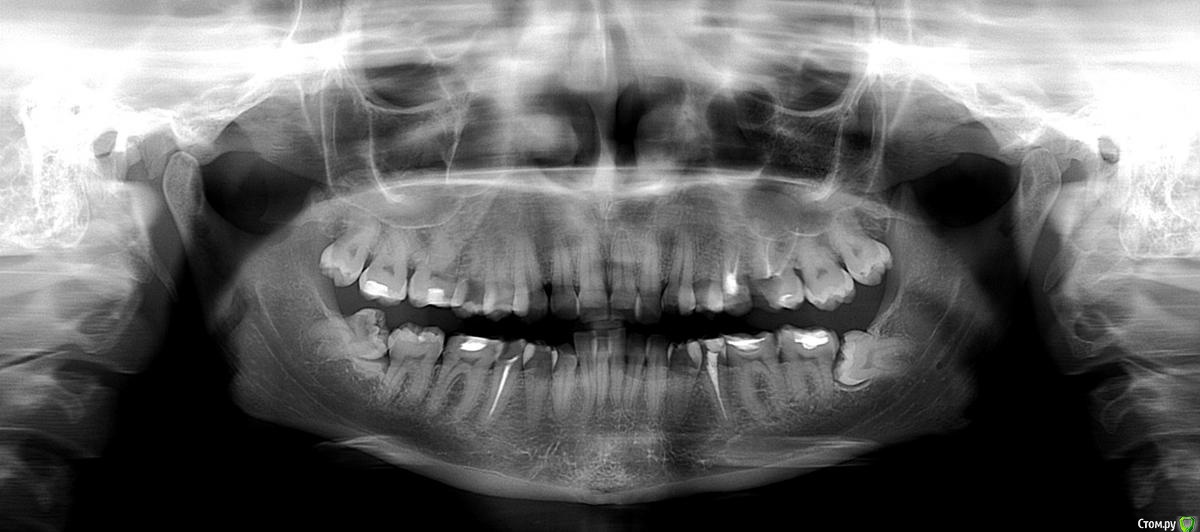

lyagushka Опубликовано 2 ноября, 2015 Поделиться Опубликовано 2 ноября, 2015 (изменено) Здравствуйте! Мне бы хотелось узнать мнения специалистов. Снимок прилагаю (мне кажется качество плохое, но есть только этот). Меня интересует соотношение верхней правой 6-ки и гайморовой пазухи: запломбированные каналы не нарушают ли ее целостности, если это возможно разглядеть? При таком расположении нижних зубов мудрости, очень сложное и травматичное грозит удаление? Если их удалять, то верхние тоже необходимо удалить? Спасибо. Снимок перевернут в зеркальном отражении (6-ка справа - справа на снимке) Изменено 2 ноября, 2015 пользователем lyagushka Ссылка на комментарий

shishok Опубликовано 2 ноября, 2015 Поделиться Опубликовано 2 ноября, 2015 Соотношение корней и дна гайморовой пазухи по 2х мерному снимку невозможно определить(только приблизительно),нужна КТ. Для удаления нижних зубов мудрости найдите доктора "с руками" и проблем не будет.Верхние восьмые тоже удалить(для профилактики их смещения). Ссылка на комментарий

diesel87 Опубликовано 2 ноября, 2015 Поделиться Опубликовано 2 ноября, 2015 Судя по снимку киста в пазухе в проекции корней этой шестёрки. Ссылка на комментарий

diesel87 Опубликовано 2 ноября, 2015 Поделиться Опубликовано 2 ноября, 2015 Каналы уже запломбированы. Что нужно делать с этой кистой? Врач, во время лечения, ничего мне о ней не говорил.Это может быть и полип в гайморовой пазухе. Надо уточнять снимками. Ссылка на комментарий